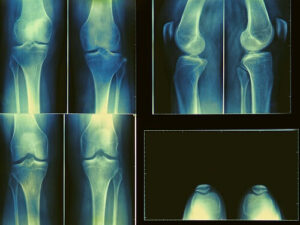

- рентгенография пораженной кости — основной метод диагностики, позволяющий выявить новообразование;

- визуальные методы (компьютерная томография (КТ), магнитно-резонансная томография (МРТ)) — методики, предоставляющие более достоверную, чем рентгенография, информацию о размере и локализации остеохондромы;